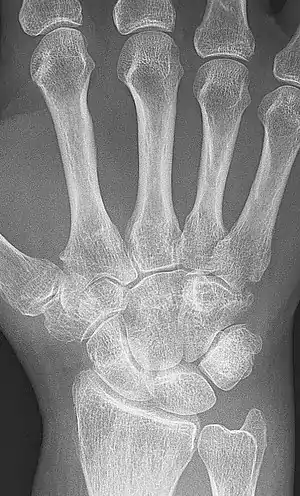

A sintomatologia clínica (rigidez prolongada e dor em uma articulação) e um raio X que revele fusão óssea é suficiente para esse diagnóstico, mas é importante identificar a causa para decidir o melhor tratamento.